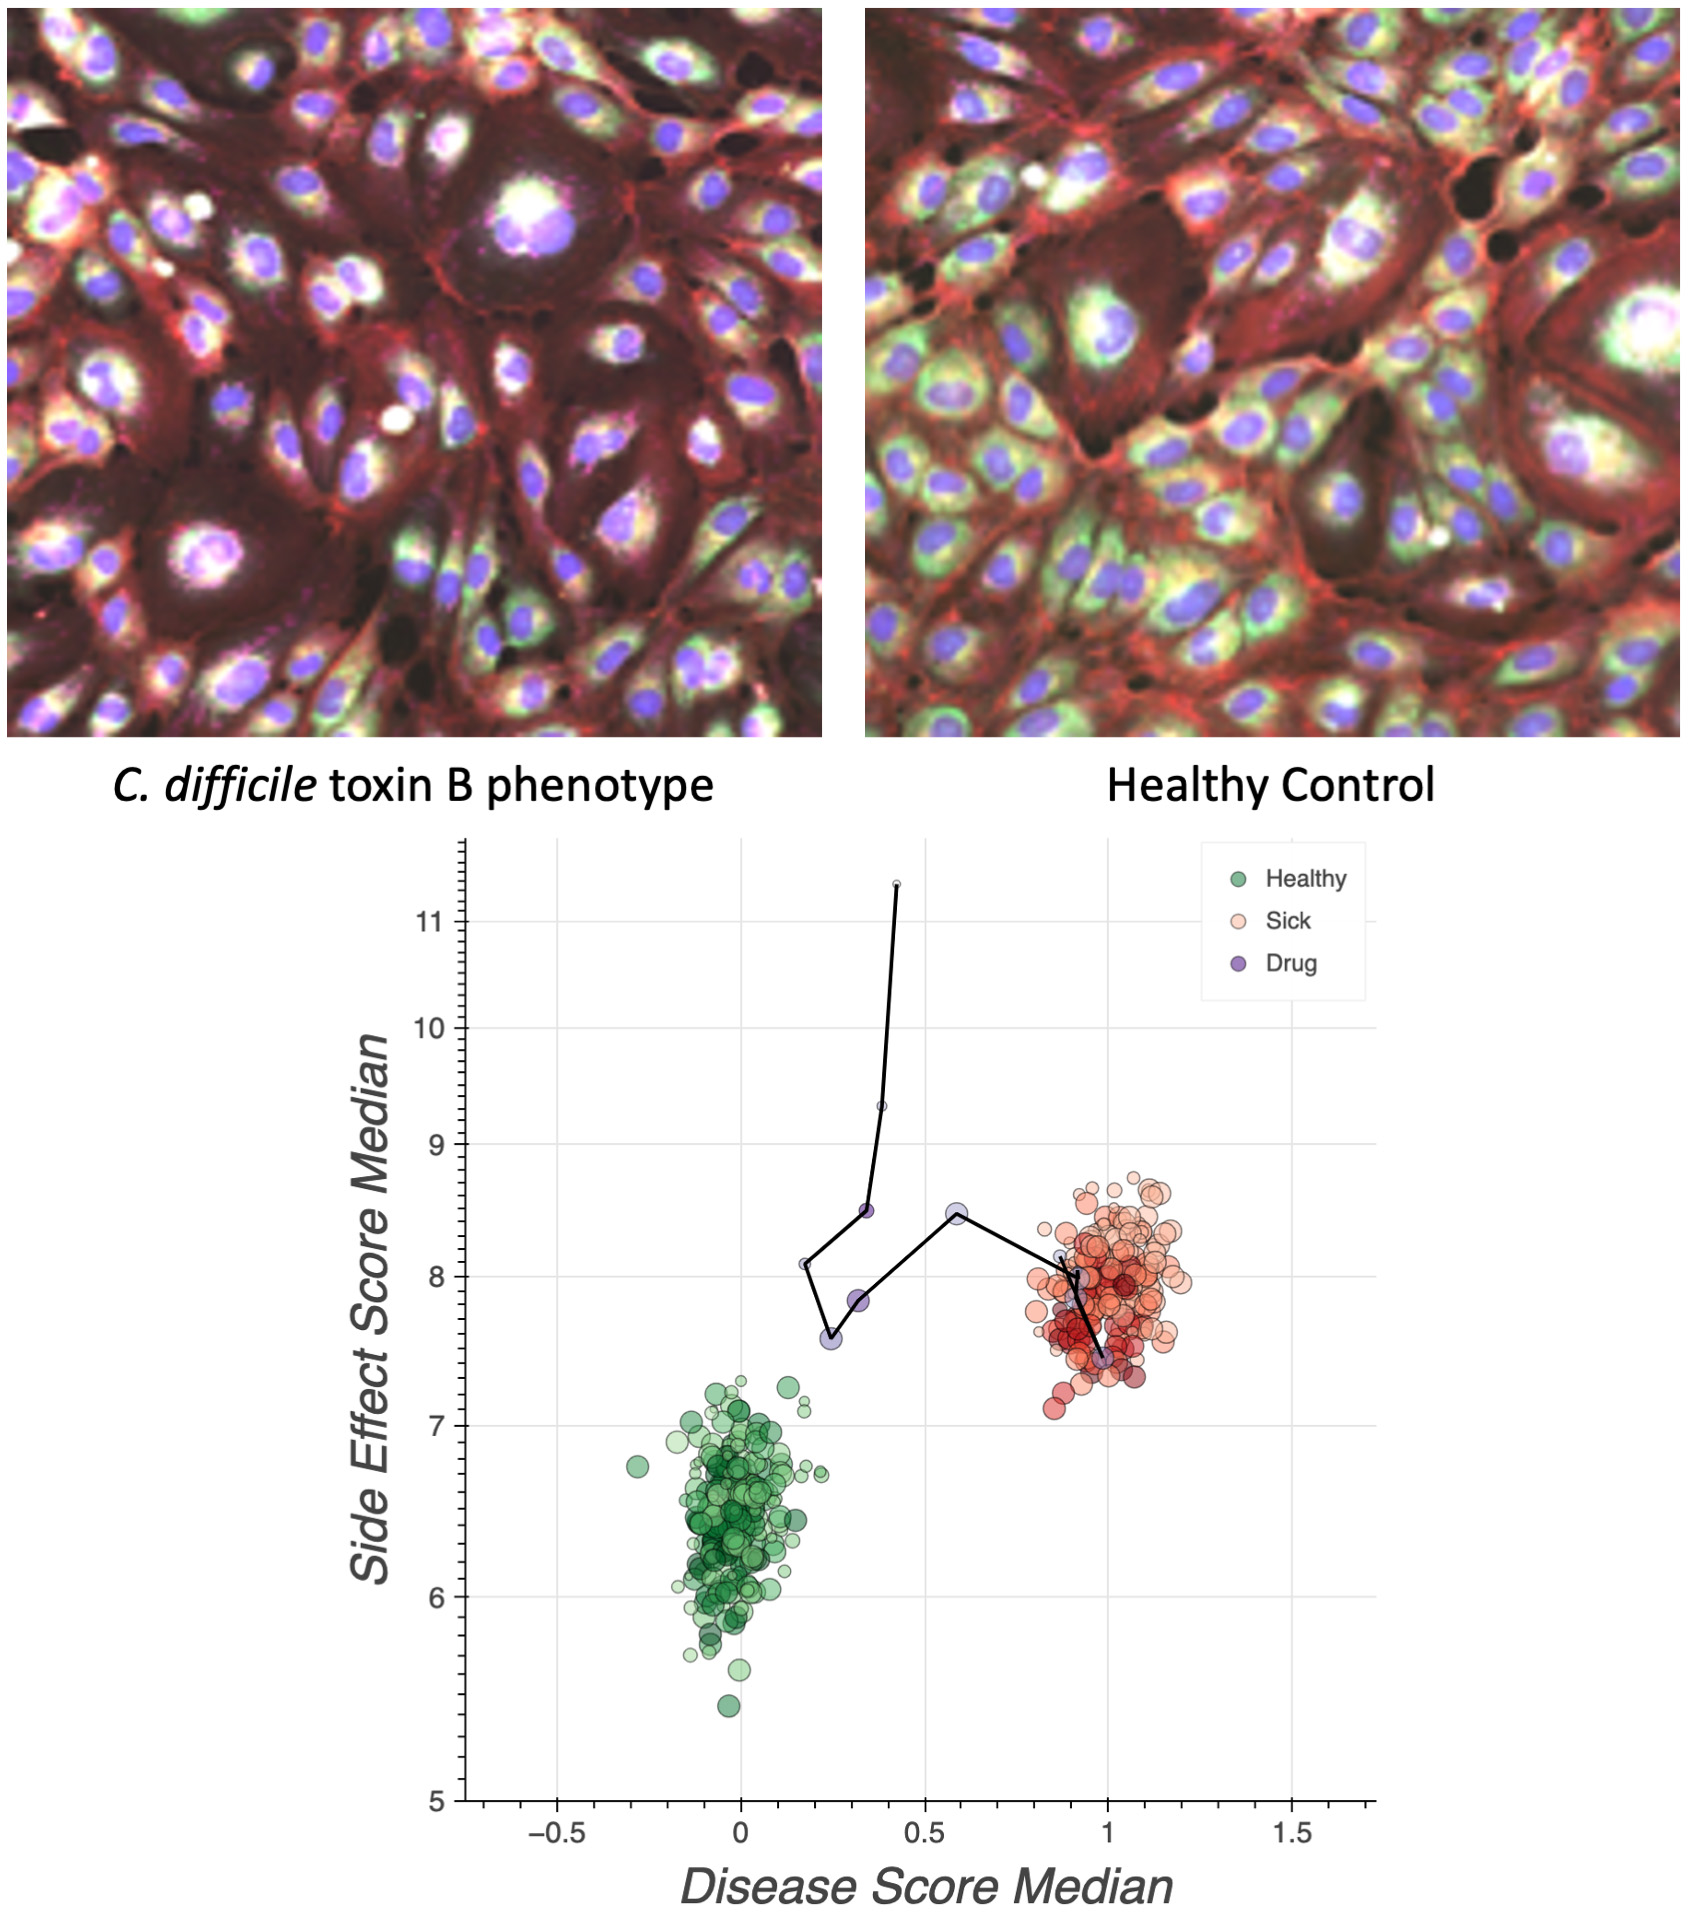

•Completed a Phase 1 study for REC-3964 in healthy volunteers for the potential treatment of Clostridioides difficile (C. difficile) infection with a favorable safety and tolerability profile